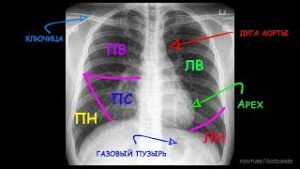

Стоит ли делать флюорографию груди при пневмонии

Одним из основных и самых простых методов диагностики различных заболеваний легких является флюорография. Исследование позволяет зарегистрировать патологические изменения строения основного органа дыхания, выявить туберкулез, рак легких, а также увидеть пневмонию. Это самый быстрый и дешевый способ диагностировать пневмонию и другие проблемы с легкими. Принцип исследования грудной клетки с помощью ФЛГ Флюорография — один из методов …